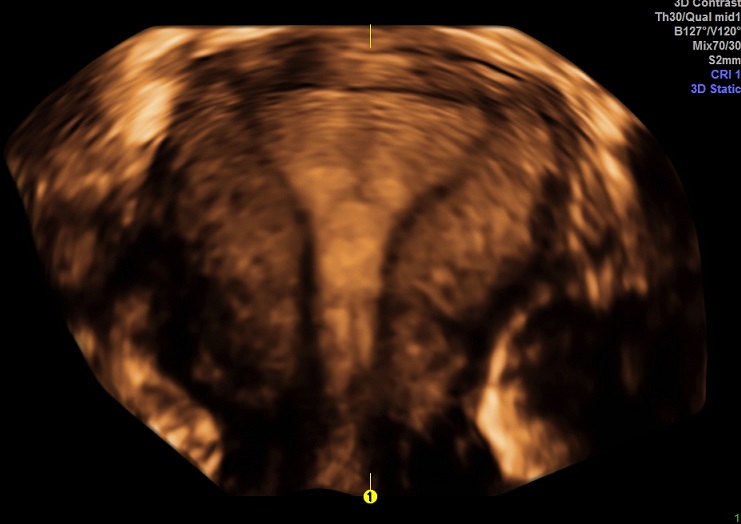

2015-2-17 月经第23天检查 黄体期 |

2015-2-17图示